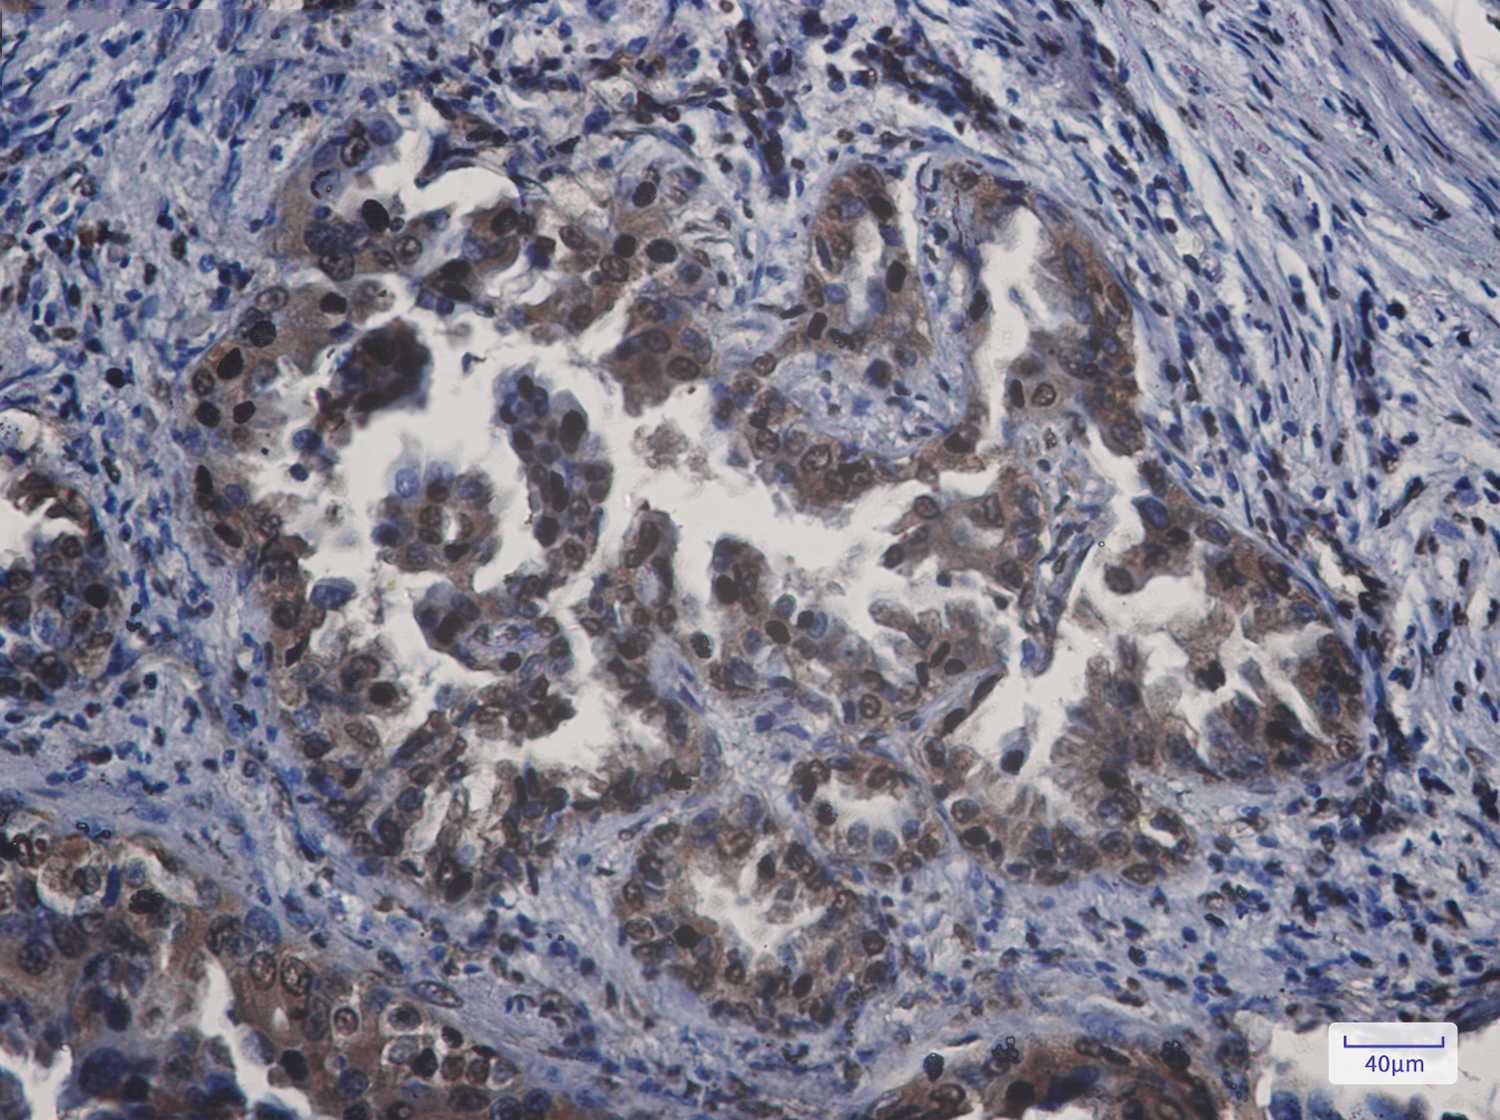

文献和实验:使用 Anti-phospho-Akt (Ser473) Rabbit mAb 对石蜡包埋的人乳腺癌组织进行免疫组织化学分析。(图 A)使用免疫组化试剂盒M&R HRP/DAB Detection IHC Kit,抗体 1:100 稀释;(图 B) 采用普通免疫组化试剂盒,抗体 1:25 稀释。 图 6 免疫组化实验检测 Erk1/2 表达 注:使用 Anti-Erk1/2 Mouse mAb与p44/42 MAPK (Erk1/2)Rabbit mAb 对正常小鼠心脏组织进行免疫